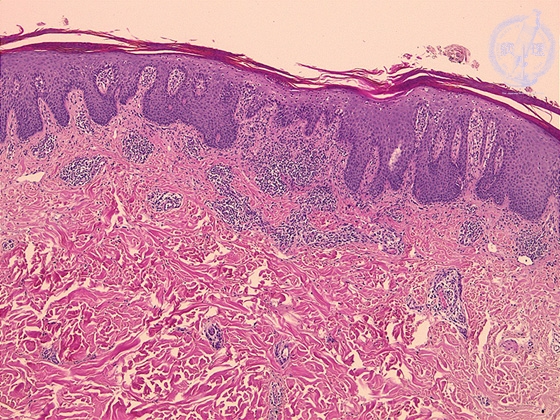

- ★(1)Psoriasis (Psoriasis vulgaris)

Microscopic image: The upper dermis shows perivascular lymphocytic infiltration. Rete ridges are elongated in a regular manner.